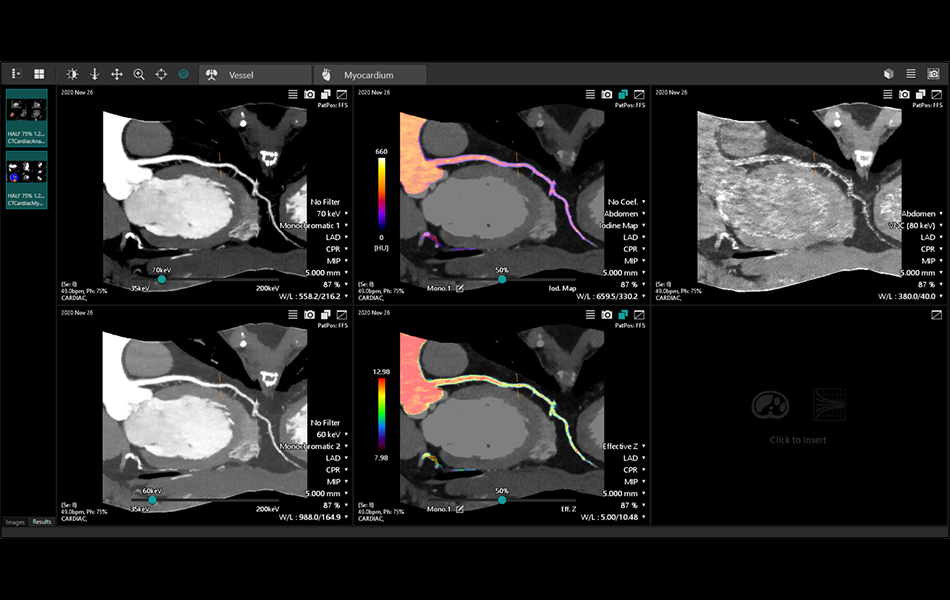

Spectral Vessel Analysis (7.15.6)

The ability to display CPR (curved plane reformat), SPR (stretched curved plane reformat) and crosscut to review coronary artery spectral image.